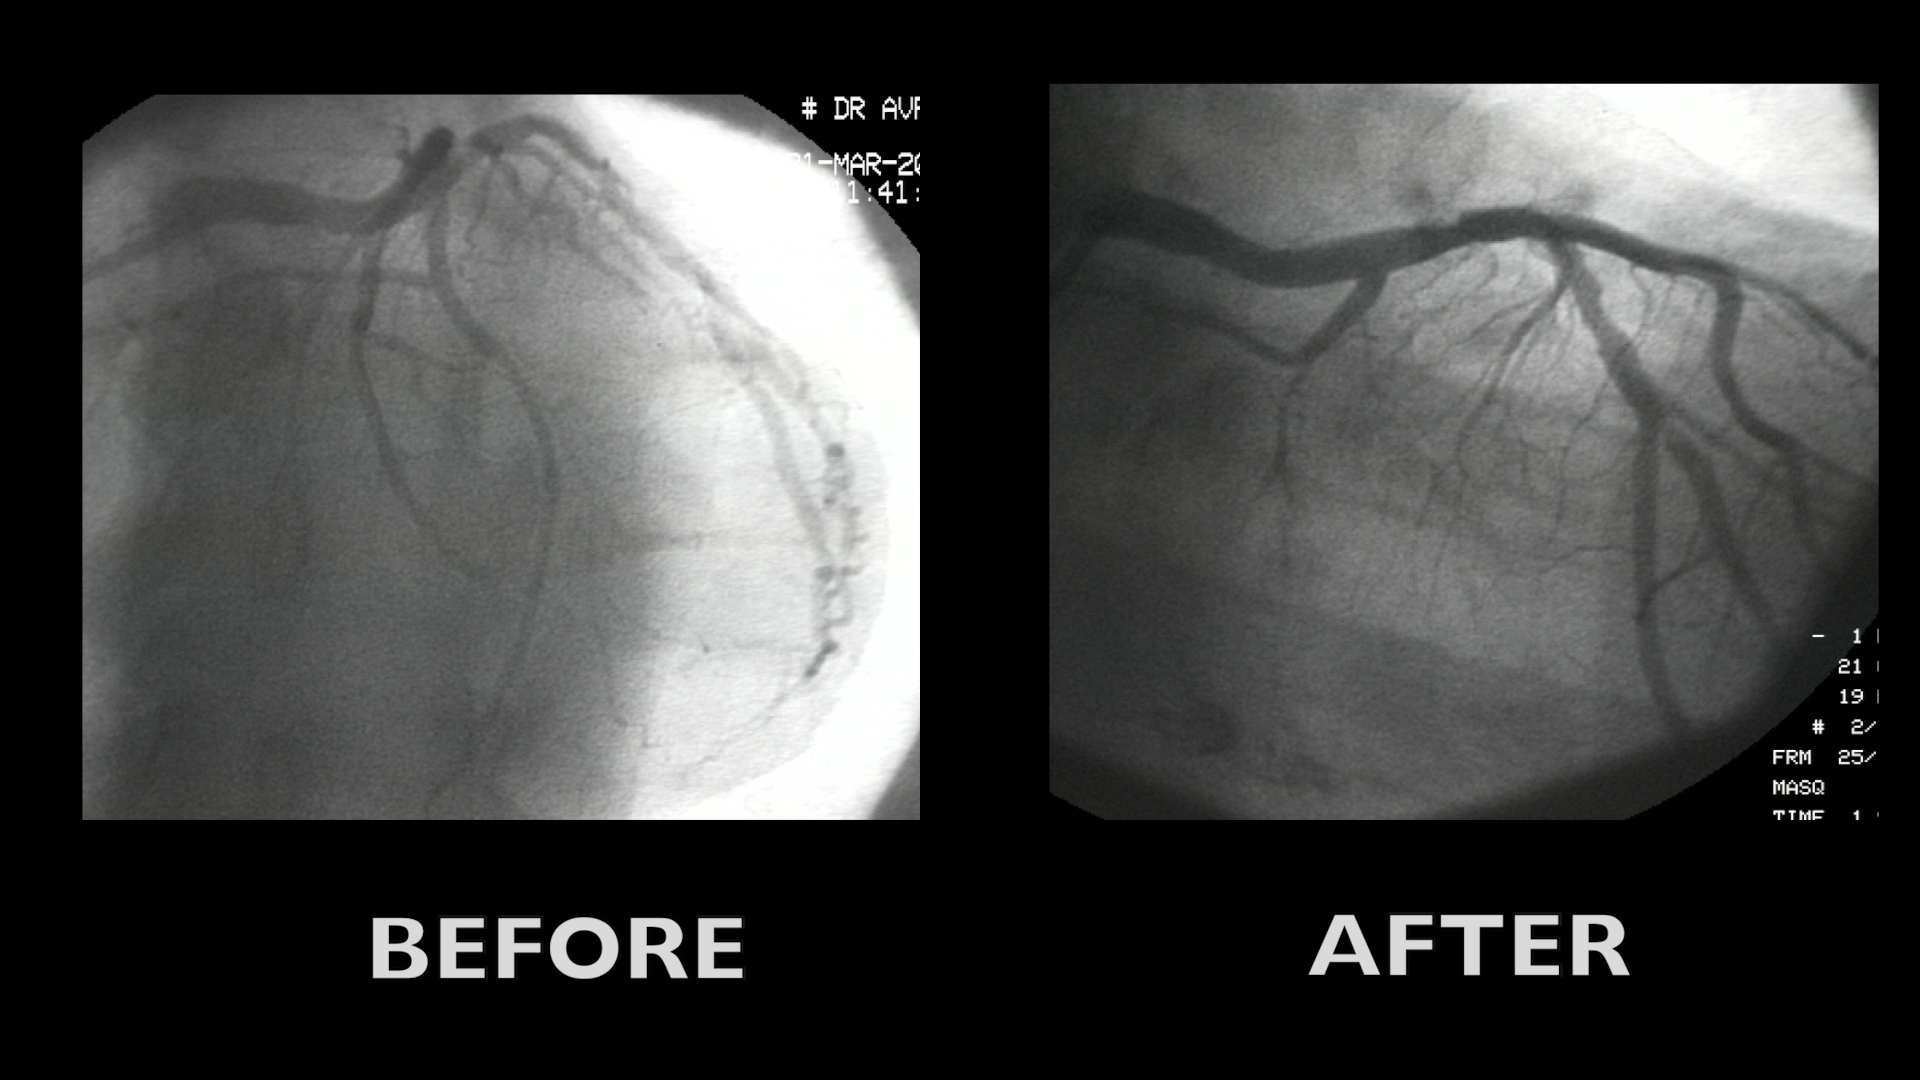

Case summary

• 1999 BMS in mid RCA

• 2007 Cypher stent in proximal RCA (small)

• 2010 Angio with CTO of stent in mid RCA

• Aggravation of symptoms in last months

• CVRF: Diabetes NID, hypetension, dyslipidemia

• CTO of mid to distal RCA

• Non significant stenosis in LAD (normal FFR)

• J-CTO-score : 2

• Blunt stump

• Long lesion

• Progress score : 0

• Anatomy:  proximal cap, stent as marker, distal portion of CTO diseased

Description of procedure

• Retrograde approach in 1st intention

• Surfing spetal

• Tip injection but no connection

• Connection successful with Sion black

• Antegrade approach

• Reverse cart (guideliner for rdv)

• Predilatation and stenting